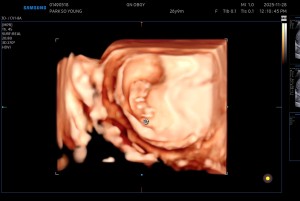

드림이 첫 정밀 본날

saxexoxo

2025-05-27